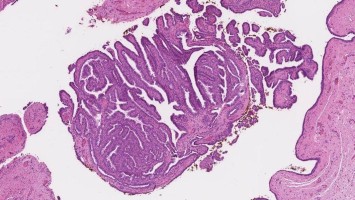

Uterine Raumforderung: Ist hier eine Hysterektomie wirklich erforderlich?

Bei einer 34-jährigen Patientin wird eine ca. drei Zentimeter große Raumforderung im Bereich des linken Tubenwinkels festgestellt. Die erste histologische Begutachtung deutet auf ein Adenokarzinom hin. Mit der Hoffnung, eine Hysterektomie zu vermeiden und den Uterus zu erhalten, sucht die Patientin nach einer Zweitmeinung. Wie wären Sie vorgegangen?